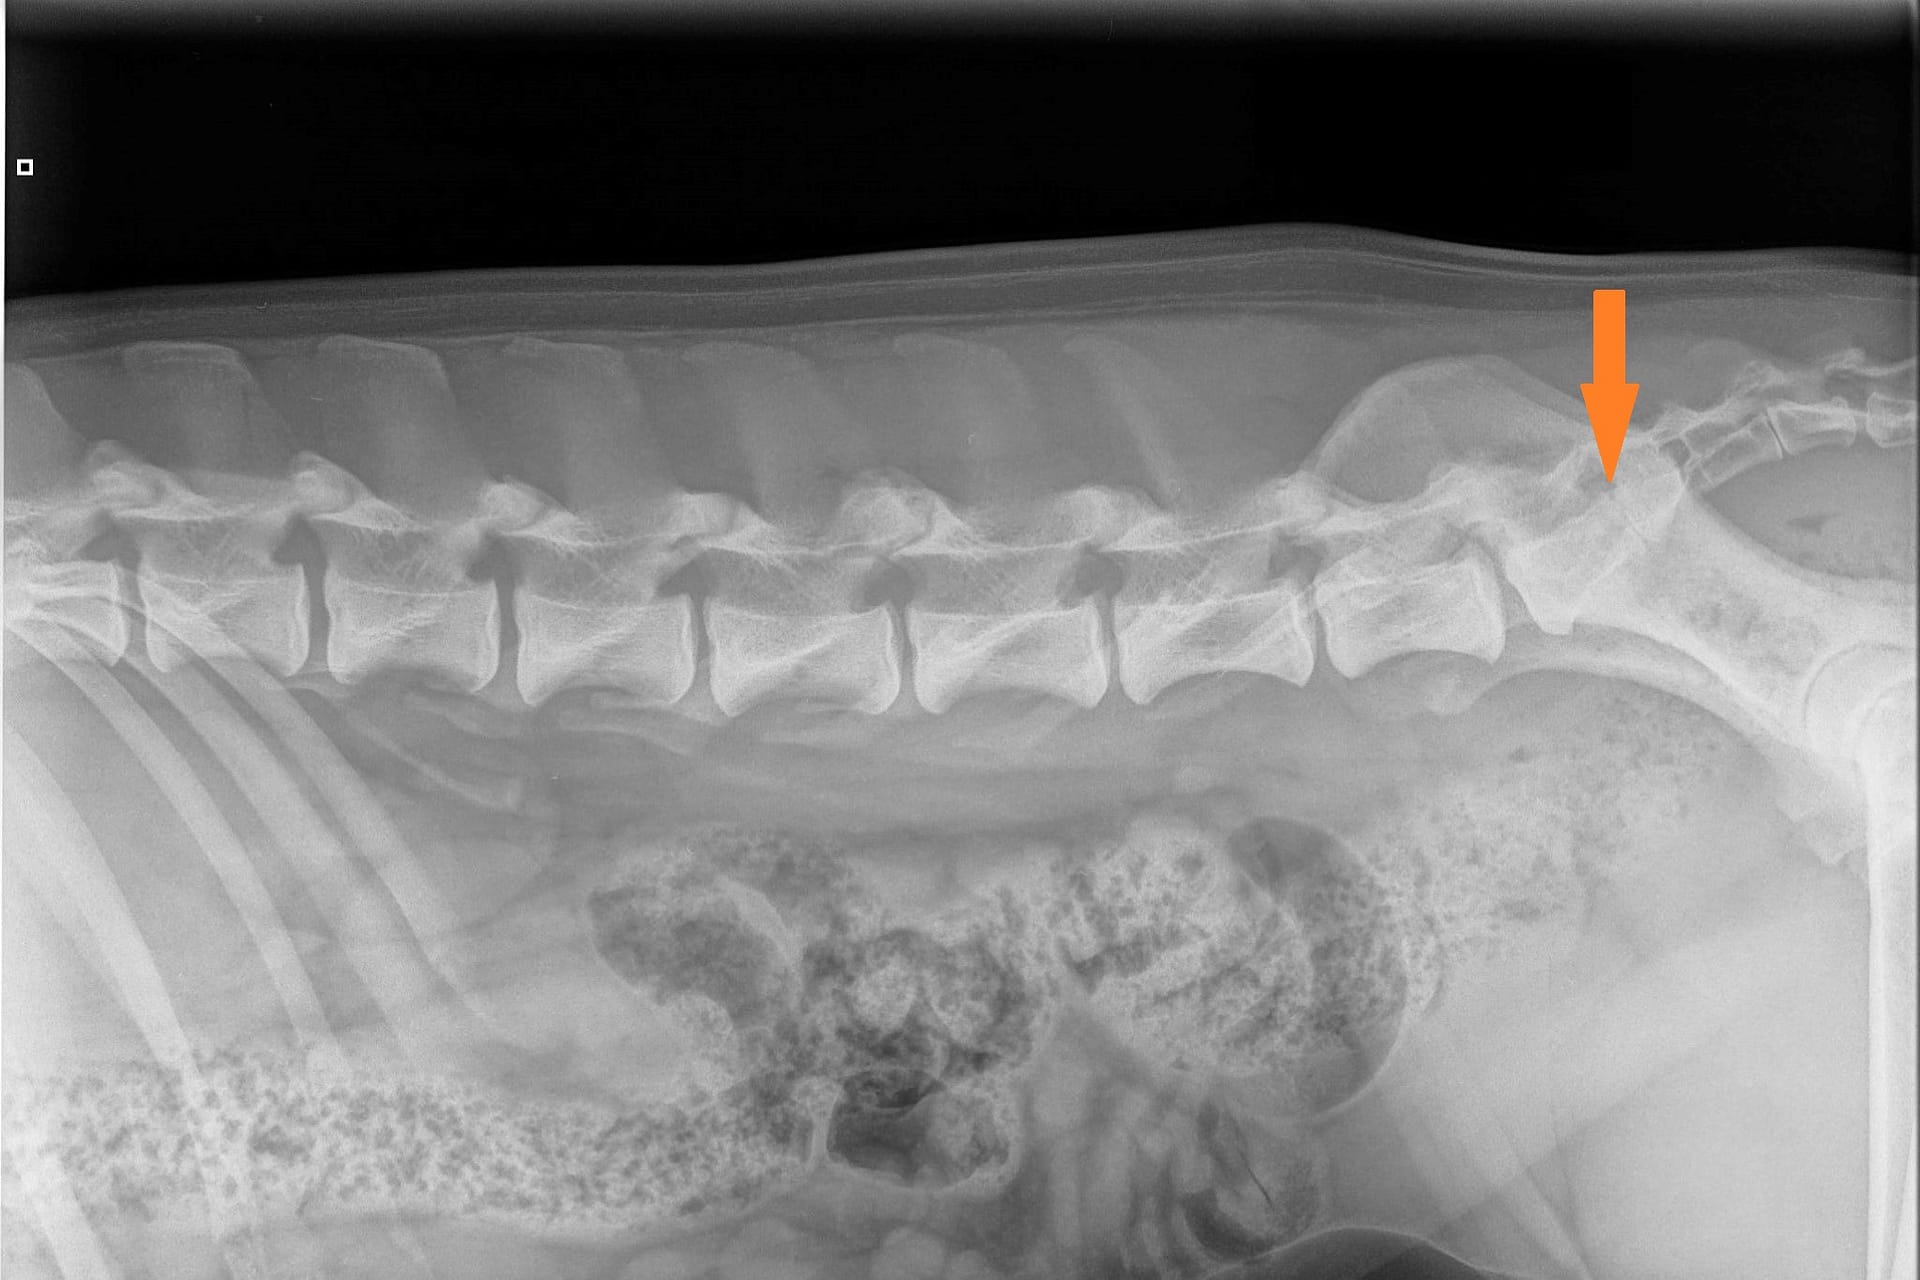

LTV4; 8 lumbar vertebras. L8 shaped like a lumbar vertebra and it has complete spinous process.

The second largest score 20% is LTV4 (6 or 8 lumbar vertebras). Most of these dogs have 8 lumbar vertebras (lumbarization).